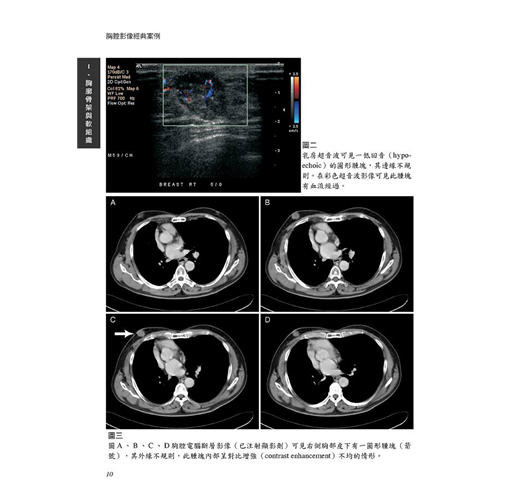

病例2 男性乳癌(Male breast cancer) 9